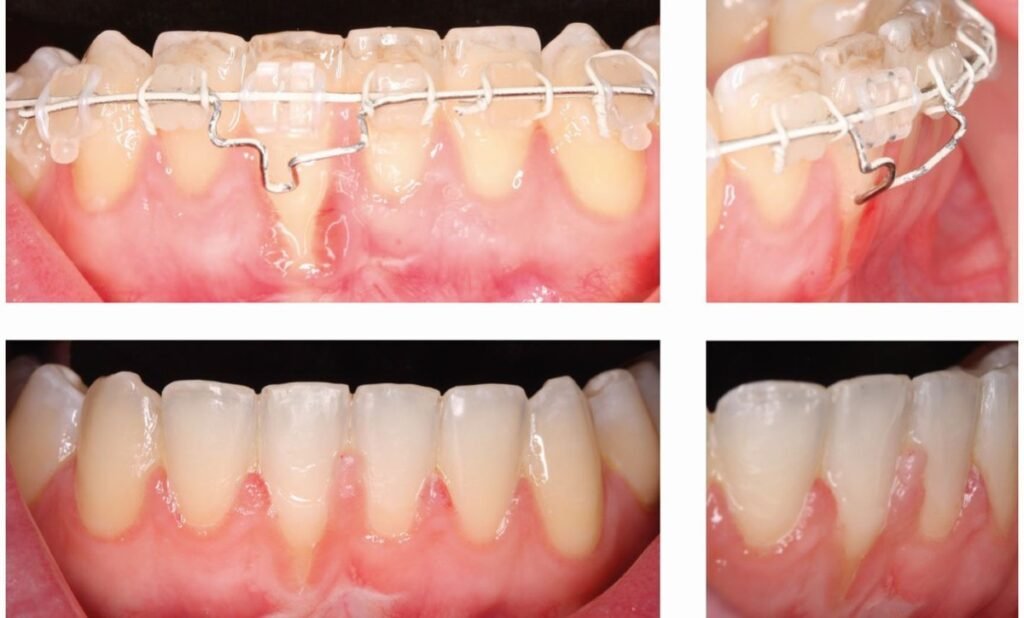

Cas Clinique 2 — Récessions multiples chez un patient orthodontique

Patiente : Femme de 28 ans, en cours de traitement orthodontique fixe depuis 18 mois. Signalee par son orthodontiste pour des récessions vestibulaires apparues en cours de traitement au niveau des incisives inférieures (43 et 41).

Présentation clinique : Récessions de 2 à 3 mm sur les faces vestibulaires des incisives 43 et 41, atteignant la ligne muco-gingivale. Tissu kératinisé résiduel quasi inexistant. Malposition dentaire initiale documentée (vestibuloversion). Septa osseux interdentaires préservés. Classification de Miller : classe II bilatérale.

Prise en charge :

- Discussion pluridisciplinaire avec l’orthodontiste : adaptation du plan de mouvement pour éviter de dépasser les limites osseuses

- Correction de la technique de brossage (brosse à poils ultrasoft recommandée)

- Monitoring mensuel pendant la phase orthodontique

- Chirurgie muco-gingivale envisagée en fin de traitement orthodontique : greffe conjonctive sous-épithéliale avec LCA ou technique tunnel

Évolution attendue : Stabilisation des récessions sous contrôle orthodontique. Recouvrement post-chirurgical favorable (70 à 100 %) si l’anatomie osseuse interdentaire est préservée.

Point pédagogique : Le déplacement orthodontique hors des limites osseuses est un facteur étiologique majeur de récession. La coopération entre l’orthodontiste et le parodontiste est indispensable pour prévenir et traiter ces complications.